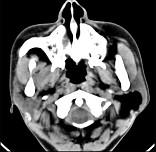

问题 女性,50岁,左侧面部肿胀,CT检查如图,应考虑为()

选项 A.左侧腮腺囊腺瘤 B.左侧腮腺囊肿 C.左侧腮腺脂肪瘤 D.左侧腮腺错构瘤 E.左侧腮腺炎

答案 C